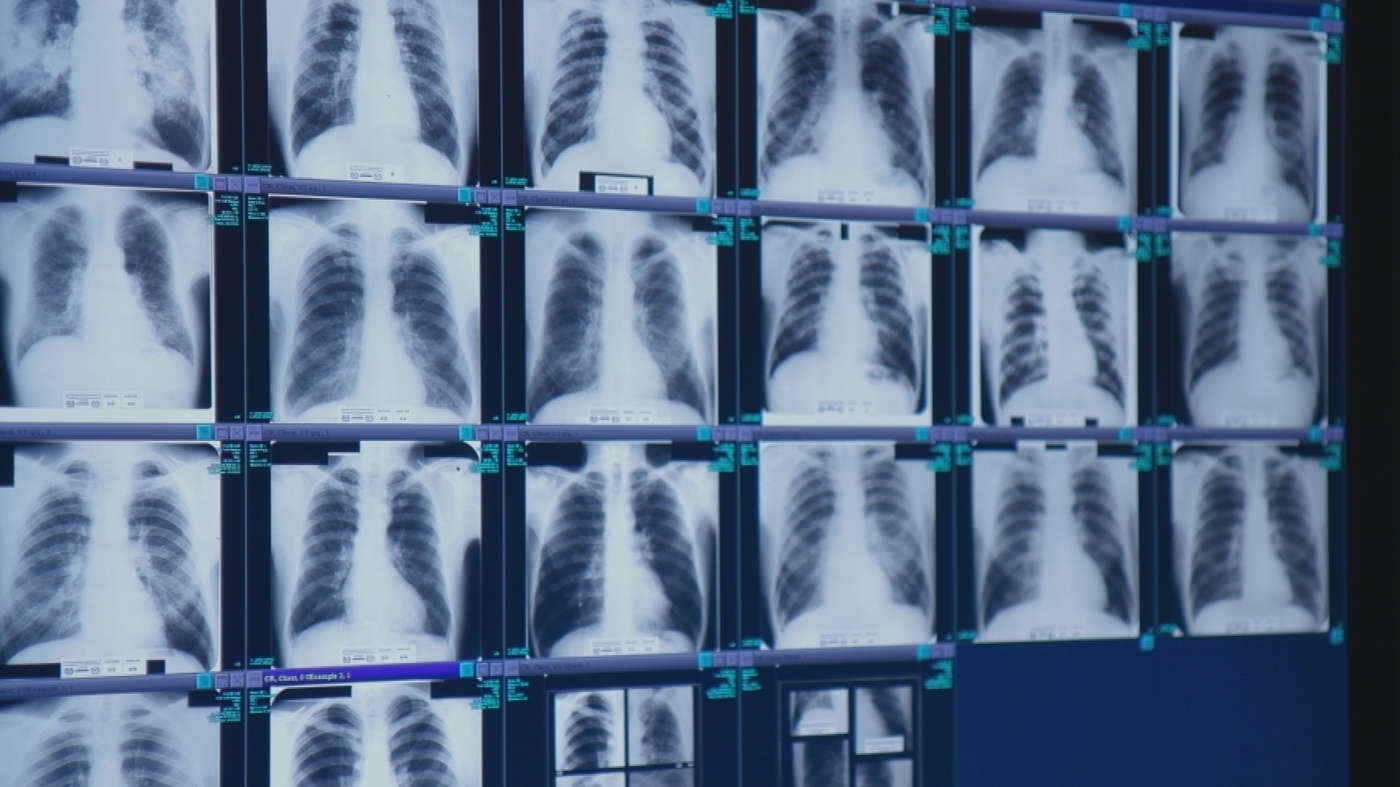

Doctors are raising alarms about a rising epidemic of silicosis, a deadly lung disease caused by inhaling silica dust from cutting quartz countertops. The condition, which causes irreversible lung scarring, is increasingly affecting workers in the stone-cutting industry, particularly those handling engineered quartz with high silica content. Many cases are underdiagnosed, delaying critical treatment. The disease is incurable and can lead to severe health issues, including the need for lung transplants. Researchers emphasize the need for better workplace safety and early screening, especially for vulnerable immigrant workers.